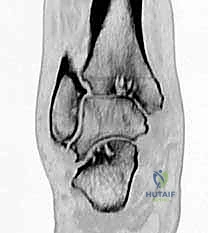

* التصوير المقطعي المحوسب (CT Scan): ضروري جداً لتقييم جودة العظام (Bone stock)، والتخطيط الجراحي الدقيق لتحديد حجم المكونات الصناعية، خاصة في حالات النخر اللاوعائي أو الكسور القديمة المعقدة.